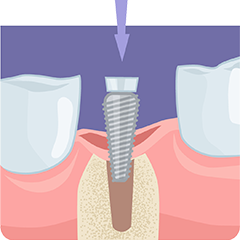

即時荷重インプラントImmediate Loading

抜歯直後にインプラントを埋入し、

その日のうちに仮歯を装着する治療法です

抜歯後すぐにインプラントを埋入し、その日のうちに仮歯を装着できる───それが即時荷重インプラントです。

すぐに咬めるようになるだけでなく、骨への刺激を保つことで骨吸収の予防にもつながります。通常は約1年かかる治療を、約4か月に短縮できるケースもあり、身体的・時間的な負担を大幅に軽減できる先進的な治療です。